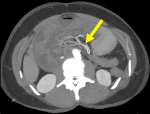

Diagnostic assessment: i) X-ray: plain abdominal radiography demonstrated small bowel air-fluid levels predominantly in the right mesogastric region, without pneumoperitoneum (Figure 1); ii) computed tomography (CT) scan: contrast-enhanced CT confirmed small bowel obstruction due to an internal hernia, with features suggestive of a right paraduodenal hernia (Figure 2-5); iii) laboratory tests: laboratory tests showed leukocytosis with a white blood cell (WBC) count of 12,400/mm3, while liver and kidney function tests, pancreatic enzymes, ionogram, C-reactive protein (CRP), and coagulation profile were all normal.

Figure 4: axial maximum intensity projection (MIP) images showing the whirl pool sign of the small intestinal mesentery with the bowel vasculature rotated 180 degrees to the right (mid gut rotaion), (yellow arrow)